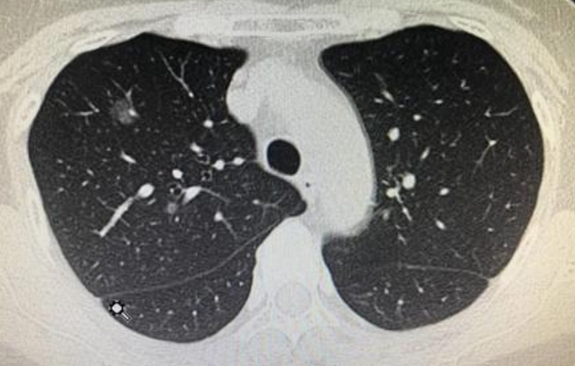

3、结节形态

CT上结节如果有下列征象需要警惕恶性可能,如:结节边缘不光滑、密度不均匀、形态不规则、有分叶、有毛刺、有胸膜牵拉、结节内小气道管壁局限性增厚、出现含气细支气管征和小泡征、偏心厚壁空洞等。恶性结节空洞通常壁厚薄不均,内壁不规则、出现壁结节是诊断恶性结节的可靠征象。此外,1cm内的实性小结节恶性概率低,而纯磨玻璃结节和部分实性磨玻璃结节恶性概率略高,需要加强随访。